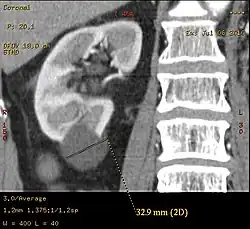

Peripelvic versus parapelvic cysts

Non-contrast CT (at left) showing peripelvic fluid accumulations, which may be hydronephrosis. CT urography (at right) reveals non-dilated calyces and pelvises. The fluid accumulations are thus peripelvic cysts.

Parapelvic cysts originate from around the kidney at the adjacent renal parenchyma, and plunge into the renal sinus. Peripelvic cysts are contained entirely within the renal sinus, possibly related to dilated lymphatic channels. When viewed on CT in absence of contrast, they can mimic hydronephrosis.[15] If symptomatic, they can be laparoscopically decorticated - removal of the outer layer or cortex.[16]